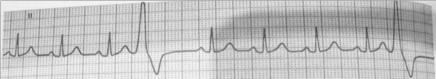

403.一成人患者心电图呈如图所示,其心律失常类型考虑为